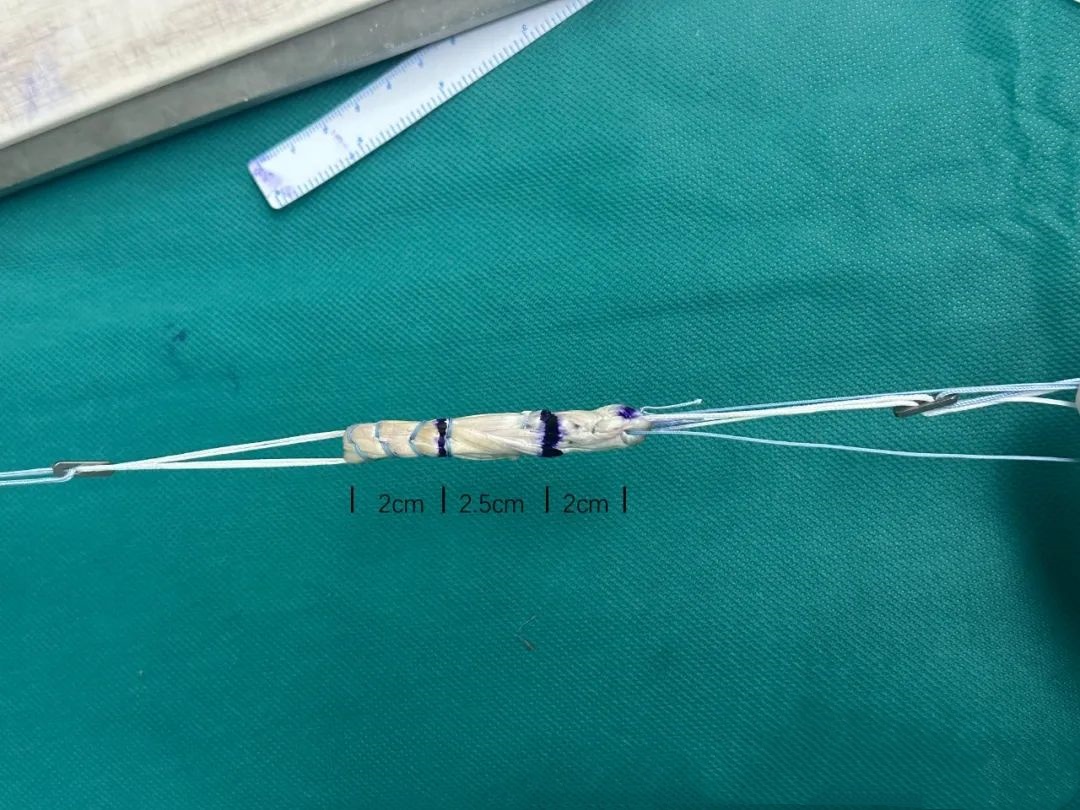

在ACL全内重建术中,对于移植物的编织方法也有很高的技术要求。于传统肌腱的简单编织缝合不同,由于全内移植物两端均使用悬吊固定,因此需要采用埋结编织法,但笔者更喜欢一种杂交改良的埋结编织法(Raul Mayr, KSSTA)。

上述的C法就是作者改良的埋结编织缝合法

测试表明,这种方法不仅缝合速度超快,而且生物力学超强

按这种方法,将自体腘绳肌腱编织成直径9mm,长度6.5cm的移植物